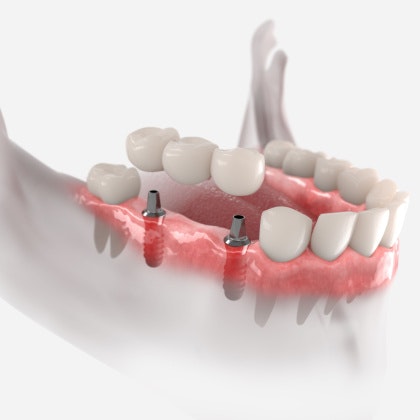

Illustration of implants placed in the jawbone

Dental implants are small titanium posts designed to replace missing tooth roots. They are surgically embedded in the jawbone and fuse with the tissue over the course of three to six months. This process is known as osseointegration. Once osseointegration is complete, the implants can support crowns, bridges, or dentures with unmatched stability.

As a periodontal practice, we cannot overstate how much of a difference dental implants can make for your oral health compared with other tooth replacement options. The main reason is their ability to stimulate the jawbone just like natural tooth roots do. They are the only treatment that offers this benefit.

Every time you bite down, your tooth roots send stimulating signals to your jawbone, which keeps it healthy. When you lose a tooth, the underlying jaw tissue quickly begins to weaken. After a certain point, this can affect your other teeth and oral structures with complications like dental misalignment, further tooth loss, and a sunken facial appearance.